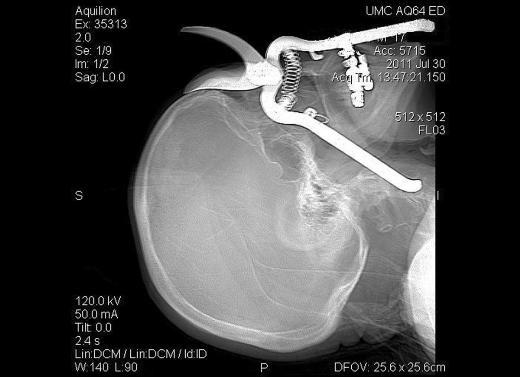

3. Bu CT scan görüntüsü ise Brezilyalı Emerson de Oliveira Abreu'ye ait. Sualtında balık tutmaya çalışırken kaza sonucu kafasına zıpkın saplanan Abreu, doktorların başarılı operasyonu sonucu kurtarıldı.

Bu CT scan görüntüsü ise Brezilyalı Emerson de Oliveira Abreu'ye ait. Sualtında balık tutmaya çalışırken kaza sonucu kafasına zıpkın saplanan Abreu, doktorların başarılı operasyonu sonucu kurtarıldı.